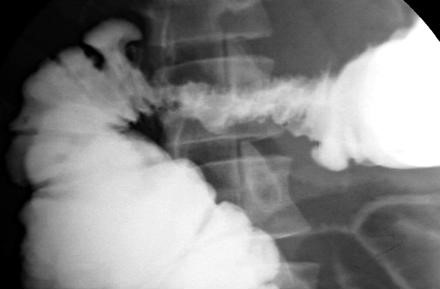

Xâm lấn trực tiếp từ khối u ác tính ngoài đại tràng hoặc trực tràng có thể xảy ra do sự kề cận, dọc theo các dây chằng. Tiền sử bệnh nhân thường cung cấp các đầu mối cho chẩn đoán. Thí dụ tiêu biểu là di căn từ ung thư biểu mô dạ dày tới đại tràng ngang qua dây chằng dạ dày-đại tràng, lòng đại tràng hẹp, các nếp dày không đều, hoặc loét (Hình 15). Ung thư biểu mô tuyến của tụy cũng có thể di căn đến đại tràng ngang theo cách tương tự. Thí dụ thí ba là ung thư vùng tiểu khung tới đại tràng sigma và trực tràng. Chụp CT cho phép đánh giá sự lan rộng toàn thể.

Hình 15. Hình chụp đại tràng thụt baryt cho thấy hẹp cứng đoạn gần của đại tràng ngang, một dấu hiệu gợi ý sự lan rộng của ung thư biểu mô dạ dày dọc theo dây chằng dạ dày-đại tràng.